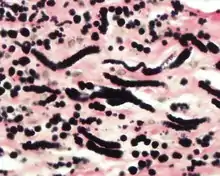

An elastic stain photomicrograph at high power highlighting the elastic fibers in black.

The elastic fibers will be highlighted by a Weigert or von Gieson elastic stains.[9]